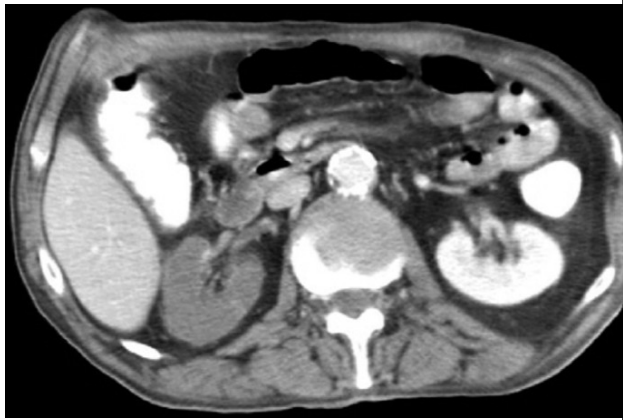

Leia o caso clínico a seguir.

J.K.W., do sexo masculino, de 67 anos, apresentou-se com início súbito de dor abdominal, com irradiação para o flanco direito 16 dias após a ressecção laparoscópica de um adenocarcinoma retal. História médica pregressa de um infarto do miocárdio há seis anos e disfunção ventricular esquerda sem terapia anticoagulante. O paciente estava febril. Dados laboratoriais mostraram uma creatinina sérica de 1,9 mg/dL (creatinina basal de 0,8 mg/dL – dois meses antes), DHL de 2.300 UI/L e contagem de leucócitos de 11.500/ L. O EAS não evidenciou leucocitúria, hematúria ou proteinúria, e o eletrocardiograma mostrou ritmo cardíaco irregular. A tomografia computadorizada com contraste intravenoso foi realizada. Imagem a seguir.

Nesse caso, qual o diagnóstico?